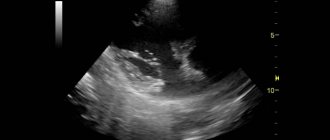

Проведение ЭхоКГ

Данная аномалия сердца выявляется только лишь при проведении ЭхоКГ. Также к обязательным методам исследования при наличии хорды являются: ЭКГ, ЭКГ с холтеровским мониторированием, велоэргометрия. Если по результатам всех исследований никаких нарушений со стороны сердца не выявлено, призывник отправляется на службу. Но редко нарушения со стороны сердца могут быть.